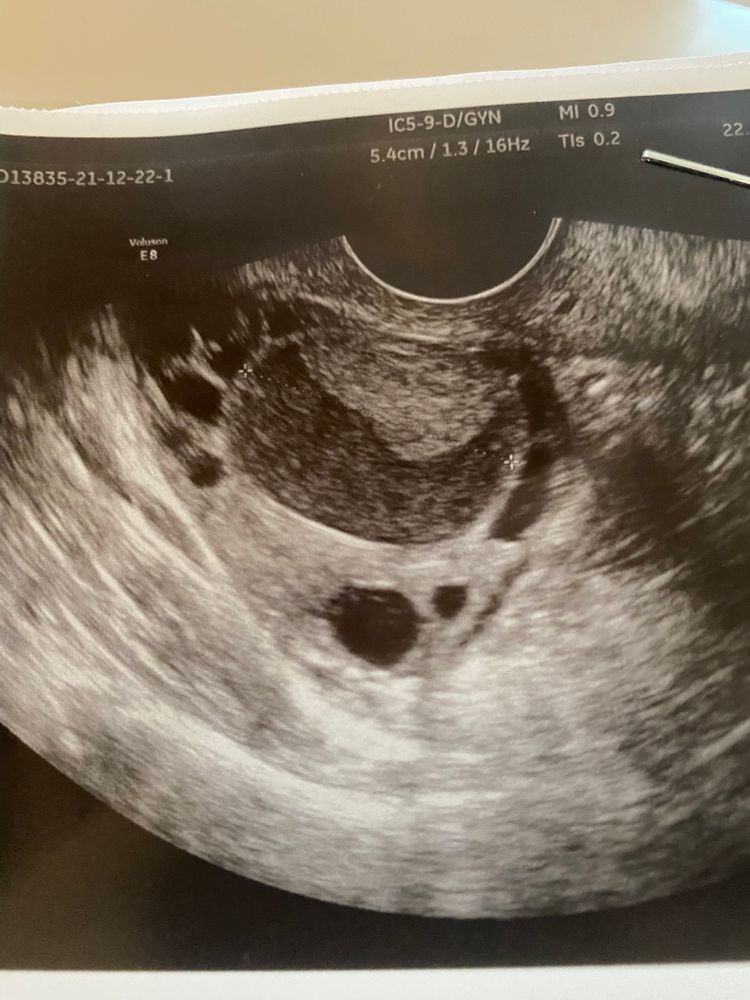

Ника Зинченко, вот, даже эндик тоньше чем в прошлые два цикла после О. Изображение

Ника Зинченко, да за него не переживаю я вообще. С ним всегда все отлично. Но вот эти кисты пугают меня, никак не могу забеременеть

Ника Зинченко, в левом ДФ 12 мм, не помню чтобы он у меня овулировал. Через два дня посмотрю, вдруг на него есть шансы

Может фоликул не лопнул? Похоже на венценосный бугорок на фолике. А что говорит узист?

Светлана Никиткова, жидкости нет вообще, была какая то недовольная, сказала что скорее всего О была вот вот и поэтому нет жидкости. Странно, в прошлом цикле жидкость нашли🤦🏻‍♀️А у меня яб и тянущая боль в яичнике началась только вчера. Хотела сегодня узнать примерно когда будет О, а отправили с признаками "киста жт с кровоизлиянием" даже не знаю что думать

Киста

В Ожидании Чуда, похоже на фолликулярную.

Киста жт? Тогда где жидкость? Толщина эндометрия